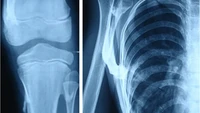

Dalam sebuah studi kasus yang diterbitkan dalam Journal of Medical Case Reports tahun 2019, seorang bocah 10 tahun dilarikan ke rumah sakit akibat benjolan-benjolan menyakitkan di tubuhnya. (Foto: Journal of Medical Case Reports)

Setelah dilakukan pemeriksaan, bocah tersebut menunjukkan gejala klinis dan radiologis dari kondisi fibrodysplasia ossificans progressiva (FOP) atau 'sindrom manusia batu'. (Foto: Journal of Medical Case Reports)

Orang dengan kondisi ini memiliki kelainan yang membuat otot, ligamen, dan jaringan lunak lainnya perlahan berubah menjadi tulang. Akibatnya tubuh terasa kaku seperti 'manusia batu'. (Foto: Journal of Medical Case Reports)